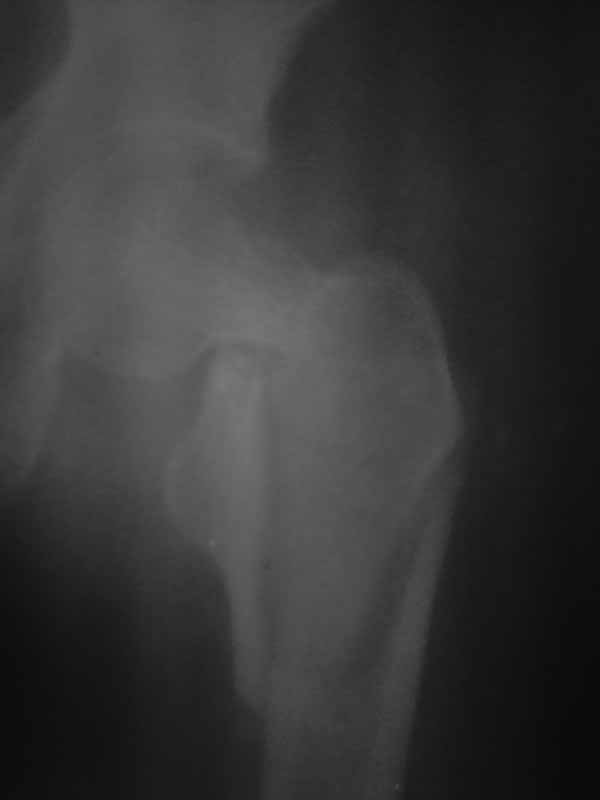

Хотелось услышать дискуссию, по-этому выложил некачественный снимок с вопросом. Стараюсь выложить немного лучше. Гамму она преобрести не сможет. Смущает то что шейка больно хлипкая и винтом развалим ее до конца. На снимке кажется что и фрагмент шейки также сломан вдоль.

Имя     : 2.jpg

Тип     : image/jpg

Размер  : 14125 байтов

Описание: отсутствует

Url     : http://weborto.net:8080/pipermail/ortho/attachments/20111002/91f177e3/attachment-0005.jpg